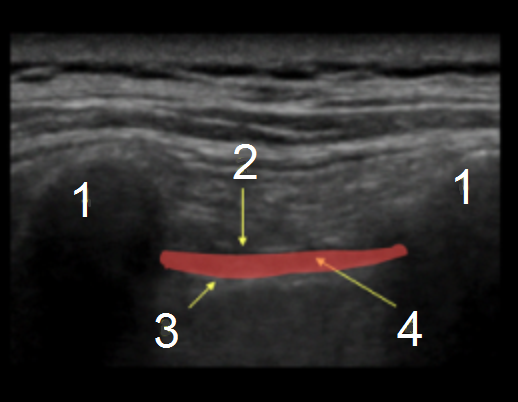

椎旁注射前旁矢状面入路图

横突

肋横韧带

胸膜

椎旁间隙